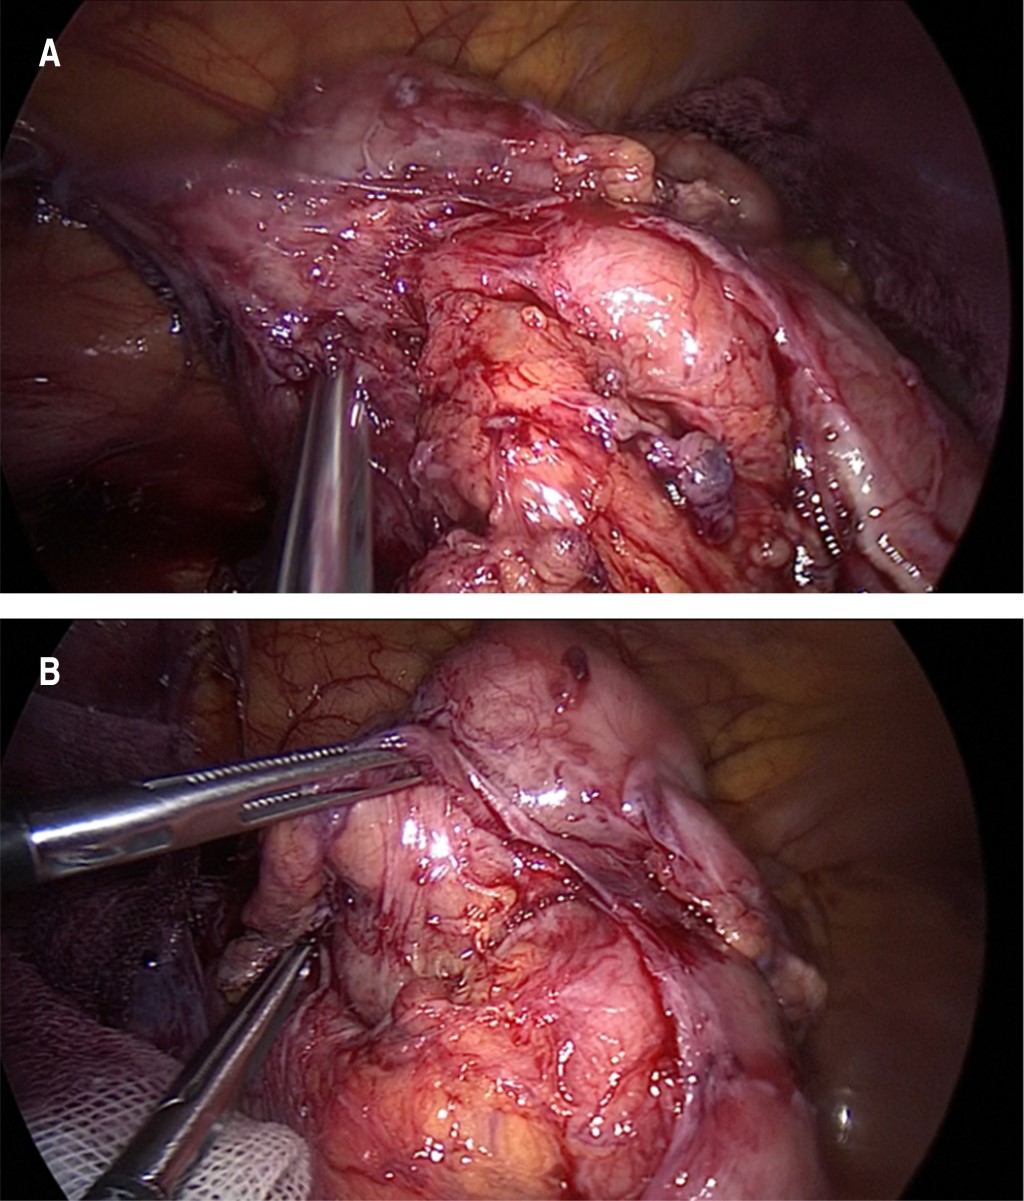

Paciente femenino de 36 años, con antecedentes familiares de diabetes mellitus por parte de su abuela materna. Niega tabaquismo, etilismo u otras toxicomanías. Antecedentes personales de enfermedad celíaca de reciente diagnóstico y apendicectomía 20 años antes. Presenta dolor abdominal difuso que se localiza en hipocondrio derecho con irradiación a región dorsal derecha acompañado de fiebre y evacuaciones disminuidas en consistencia, inicialmente tratada con paracetamol y antibióticos de amplio espectro, sin presentar mejoría, por lo que es revalorada. A la exploración física se observa paciente con taquicardia, febril, ligeramente deshidratada, con datos de irritación peritoneal (rebote en cuadrante inferior derecho del abdomen). En la tomografía de abdomen se observa una imagen compatible con apendicitis de muñón, con fecalito hacia la punta (Figura 1). Se reporta por imagenología: "Proceso inflamatorio a nivel de la fosa iliaca derecha sugiere como primera posibilidad diagnóstica apendicitis de muñón con presencia de plastrón. Imagen que sugiere apendicolito. Adenopatías pericecales y perineales de apariencia inflamatoria". La paciente pasa a laparoscopia diagnóstica donde se encuentra plastrón inflamatorio en región de ciego que no se puede disecar de manera adecuada (Figura 2A y B ). Se realiza conversión a laparotomía, encontrando muñón apendicular largo, abscedado y con afectación de válvula ileocecal, por lo que se realiza ileocequectomía y anastomosis latero lateral mecánica con engrapadora lineal cortante. El reporte de patología indica "hallazgos compatibles con apendicitis aguda". La paciente evoluciona adecuadamente en el postoperatorio.

Figura 2